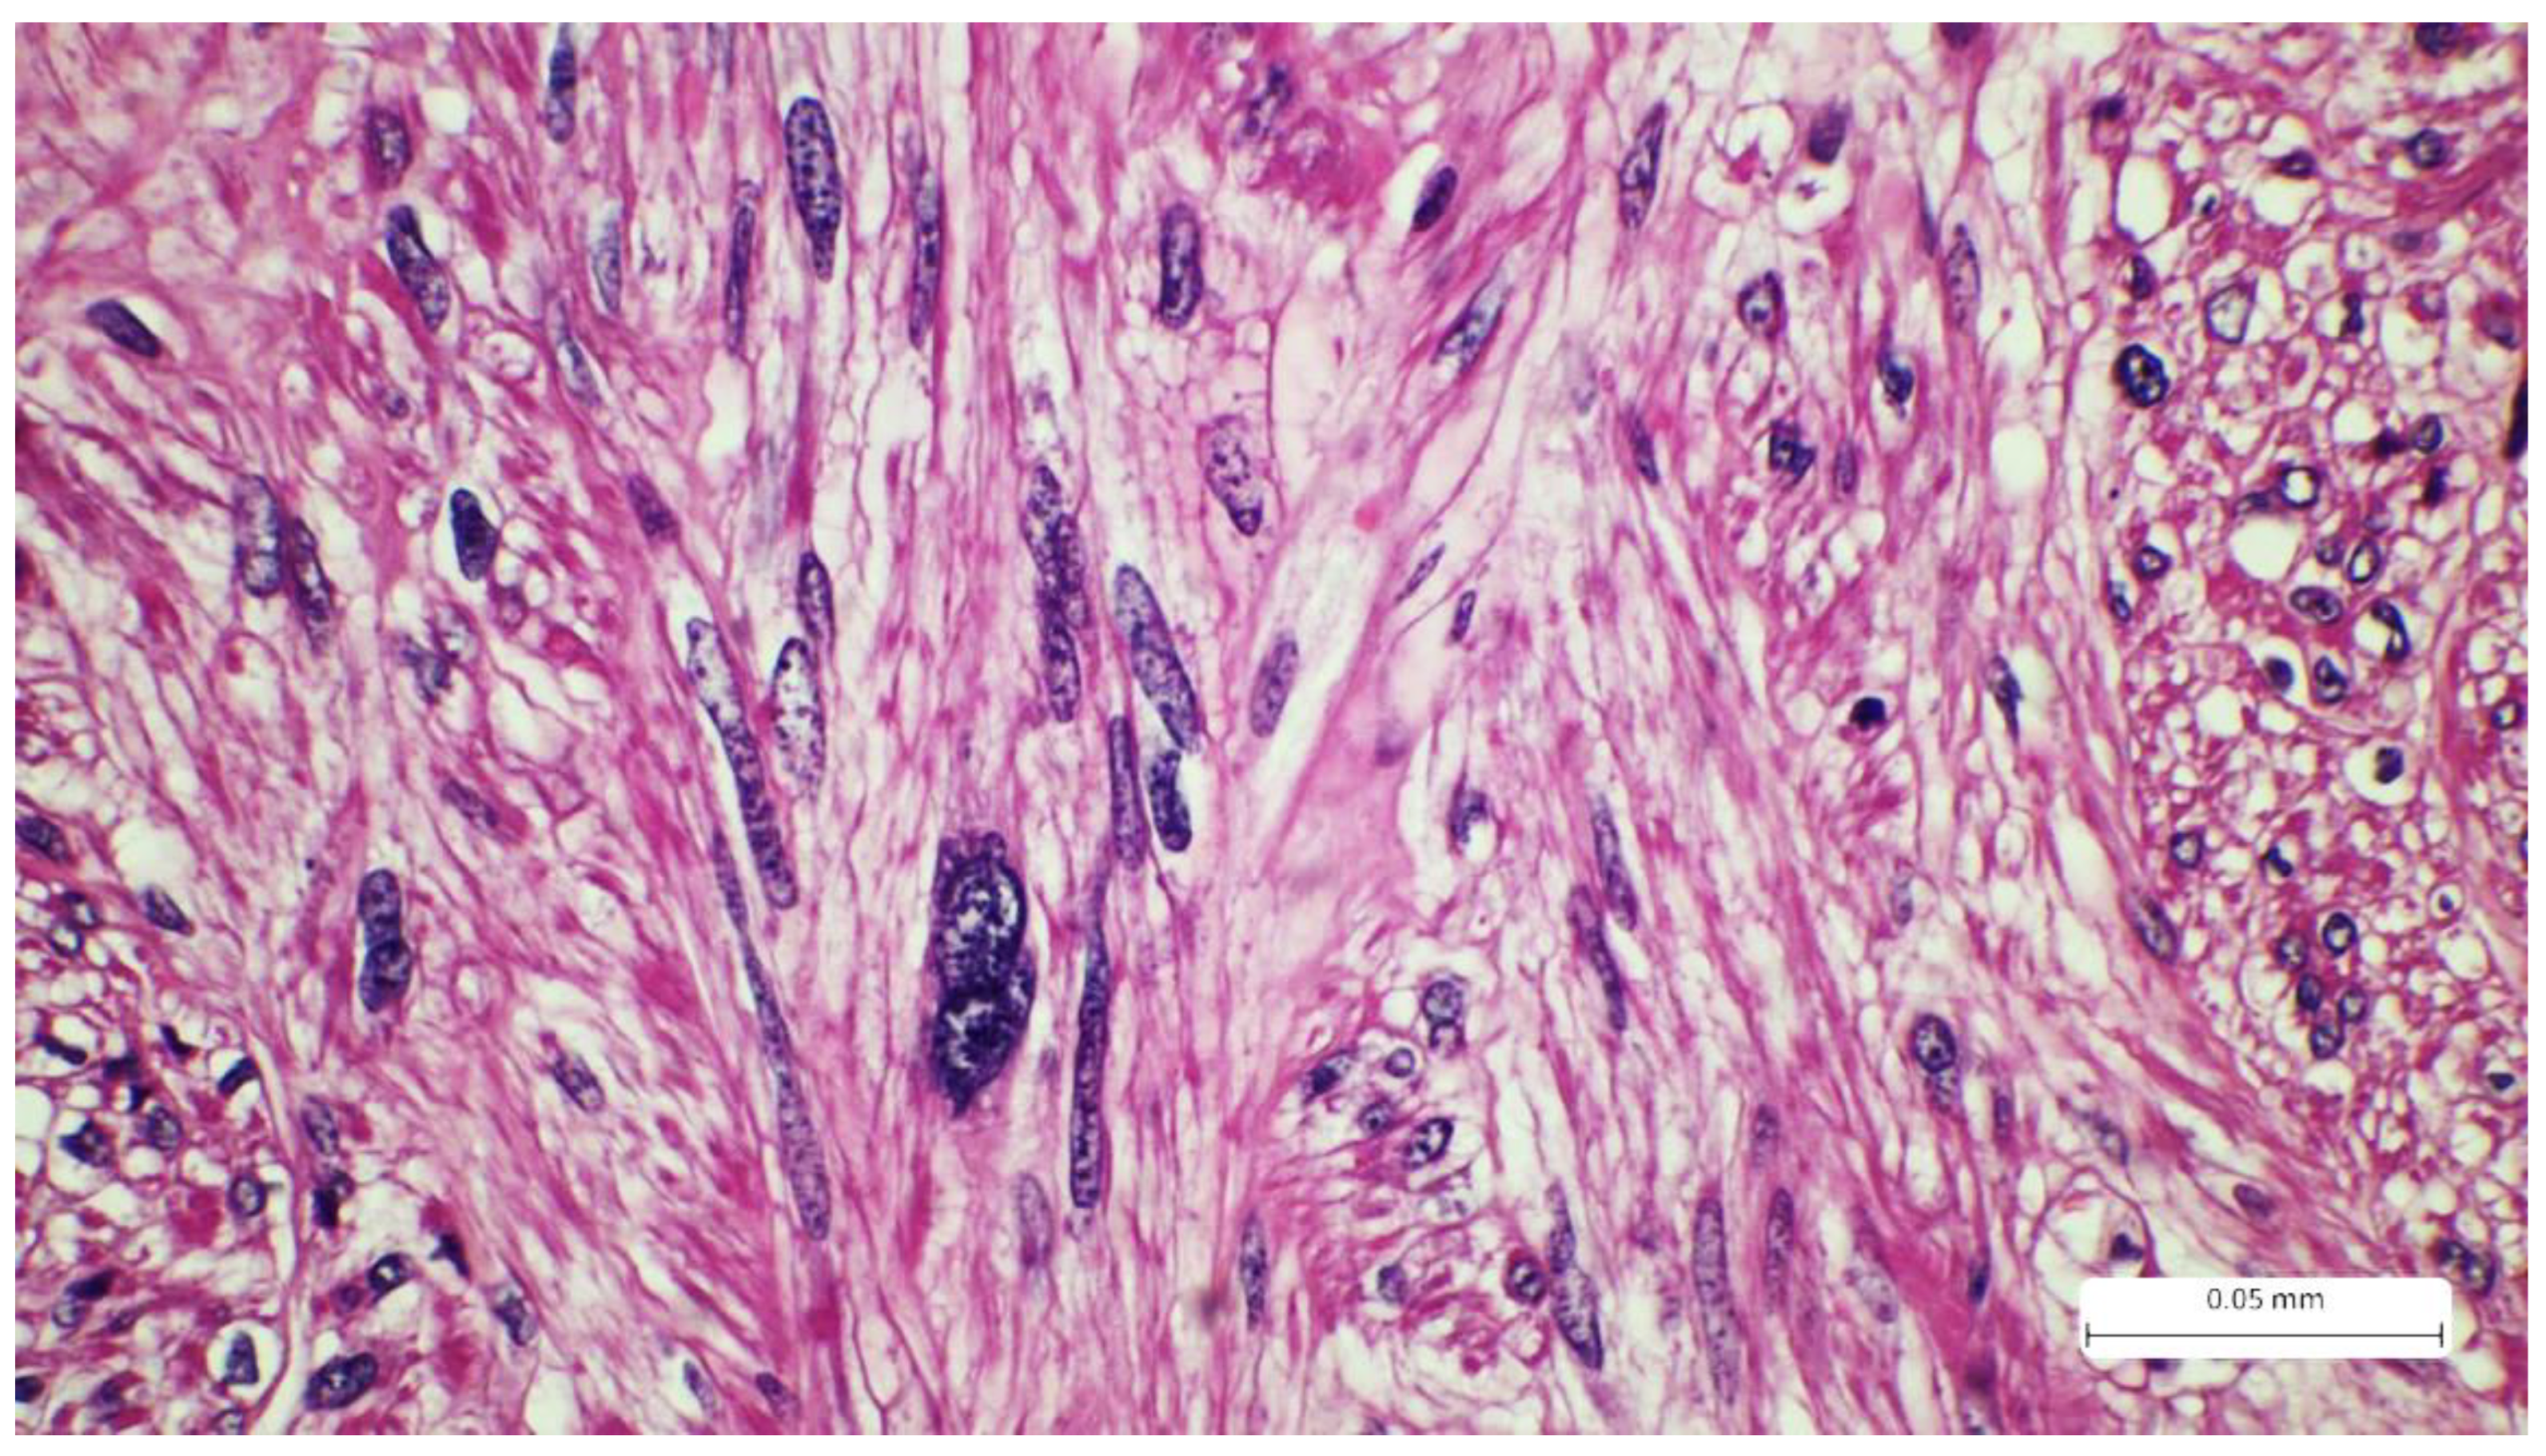

Figure 2. Tumor proliferation consists of intersecting fascicles of atypical spindle cells separated by fine bundles of collagen. The tumor cells present eosinophilic cytoplasm and elongated, hyperchromatic nuclei, with a cigar shape (arrow). A minimal inflammatory infiltrate can also be seen in the tumor stroma (Hematoxylin-eosin).

The initial excision (September 2021) consisted of a cutaneous sample measuring 36 x 10 mm, with a thickness of 25 mm, and presented a firm, white area of 30 x 9x 24 mm on the cut section. Histological analysis using the usual Hematoxylin-eosin staining revealed a solid tumor proliferation in the reticular dermis. The tumor was composed of fascicles of spindle cells with visible storiform areas. The tumor cells showed eosinophilic cytoplasm, elongated and enlarged nuclei with irregular borders, and a cigar-shaped appearance. Some cells exhibited high pleomorphism, with hyperchromatic and lobulated nuclei. The mitotic index was 15/10 HPF. Necrosis and lymphatic or vascular invasion were not identified. The tumor infiltrated the deep surgical resection margin.

Microscopic examination of the tumor samples provides crucial data for the patient’s prognosis. On the HE stains, we can observe details regarding the tumor's architecture and cytology. Typically, LMS presents solid proliferation, with tumor cells arranged in fascicles with storiform patterns. The cells are spindle-shaped, with eosinophilic cytoplasm and elongated nuclei that have a cigar-shaped appearance. Pleomorphism and atypia are evident, and the mitotic count is commonly high [1,15]. Despite these characteristics, HE staining alone is insufficient for diagnosis, as LMS can exhibit variability in these features and resemble other sarcomas with similar patterns (for example, tumors of neural or melanocytic origin). Thus, confirmation of the diagnosis is required, and immunohistochemistry is performed. Markers such as SMA (smooth muscle actin), desmin, and caldesmon are used to determine the myogenic origin. The tumor should be positive for at least two of these markers. Our case showed positivity for SMA and desmin. Caldesmon was not performed due to limited availability in our laboratory. Additionally, the Ki-67 proliferation index was expressed in 30% of the tumor cells. Neural origin (malignant peripheral nerve sheath tumor) and melanocytic origin (spindle cell melanoma) were excluded based on IHC, not only due to positivity for myogenic markers but also due to negativity for S100. For spindle cell melanoma, markers like PRAME and SOX10 would exhibit higher specificity, but S100 is highly sensitive for melanocytic lineage. Atypical fibroxanthoma (AFX), a key differential diagnosis of LMS, was also excluded because the CD68 marker was negative. AFX also presents additional details such as the presence of epithelioid or multinucleated cells, which were absent in our case. Other spindle cell tumors, such as dermatofibrosarcoma protuberans (DFSP), also enter the differential diagnosis. However, this neoplasm typically exhibits a storiform pattern with invasion of the hypodermis, a classic aspect known as “honeycomb”, a feature which is absent in the usual stain in our case. In addition, the mitotic index is low, and the tumor exhibits CD34 positivity. The CD34 marker is essential for DFSP diagnosis and differential diagnoses with storiform tumors, and its positivity excludes LMS [16,17,18,19,20,21].